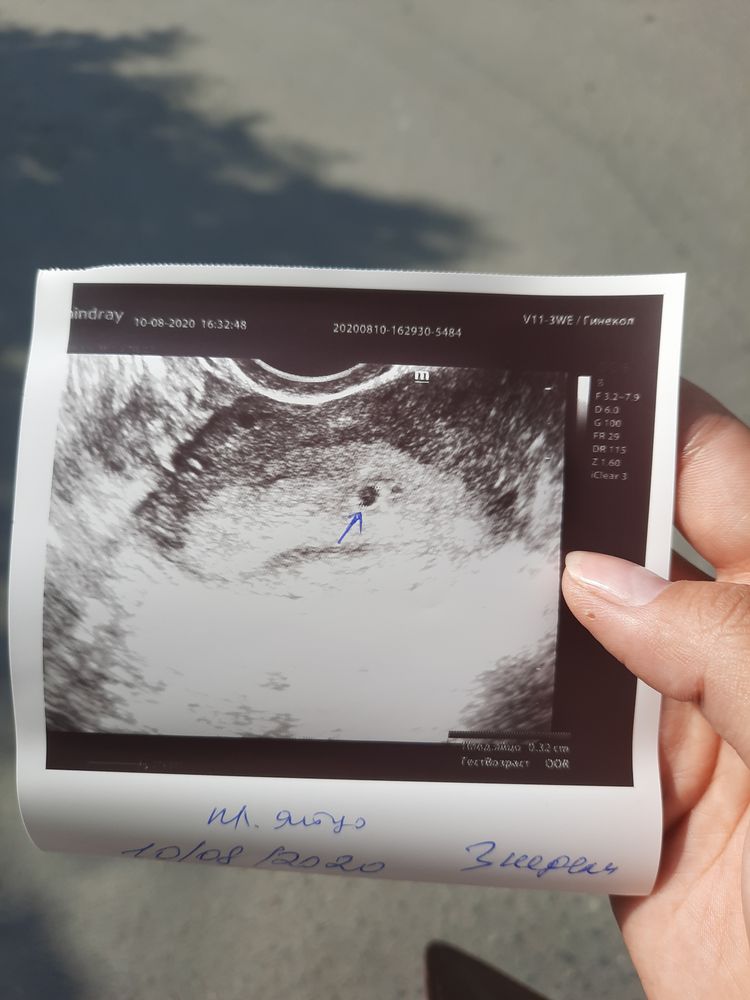

УЗИ, КТГ, доплерЗдравствуйте девочки , 1.5 недели назад была на узи, беременность обнаружили:)

Меня смущает одно, на узи увидели одно плодное яйцо(стрелкой указано), посмотрите выше слева разве не второе ?